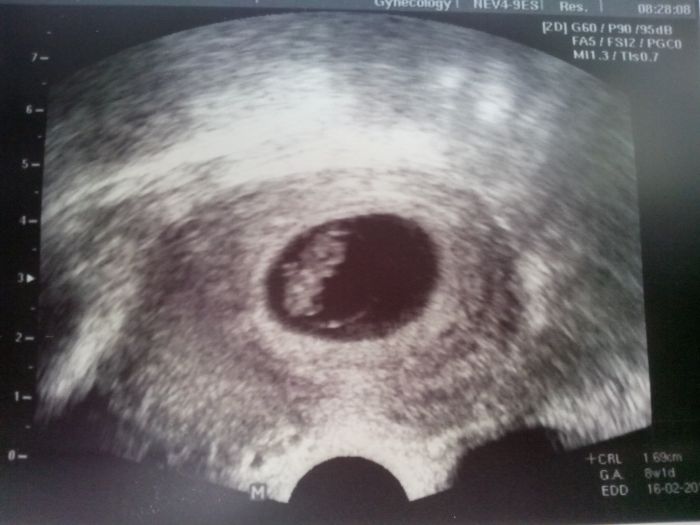

Já se nezdávám, první těhu jsem končila v 8tt a čtvrté v 10tt, na zákrok jdu až v pátek, což nevím jak dám, můsím udělat dort malí, v sobotu má narozky už 8let, děti taky nechápou jak je možný že mimi nebude, proč ho nezachrání, nevím jak jim to vysvětlit, a už plánujou nový